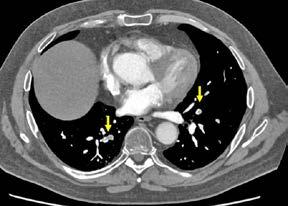

El día 18/2/2022 el paciente refiere dolor torácico. Se realiza un electrocardiograma, que muestra elevación del segmento ST en las derivaciones anteriores en relación con un infarto agudo de miocardio (IAM) anterior. Se activa código infarto y se realiza una coronariografía emergente, que muestra una oclusión de perfil embólico en la arteria descendente anterior media (Figura 1, flecha amarilla). Se trata con trombectomía aspirativa con buen resultado angiográfico final con flujo TIMI 3. Se inicia tratamiento con perfusión de heparina sódica. El día 19/2 el paciente comienza con cefalea muy intensa y afasia, por lo que se activa nuevamente código ictus y se realiza un angioTAC craneal que muestra una hemorragia subaracnoidea (HSA) de predominio izquierdo secundaria a sangrado por un aneurisma disecante de la rama M2 de la arteria cerebral media izquierda (Figura 2, flecha amarilla). Se decide completar estudio con una angiografía que confirma los hallazgos del TAC. Por el alto riesgo de resangrado y la necesidad de anticoagulación oral permanente, se decide embolización del aneurisma con coils, que resulta exitoso (Figura 3, flecha amarilla). Se reinicia durante el ingreso perfusión de heparina sódica y unos días antes del alta se comienza con anticoagulación oral con apixaban 5 mg/12 horas. La evolución clínica es favorable, siendo la exploración física al alta normal. Tras tres años de seguimiento bajo tratamiento con apixaban 5 mg/12 horas no han sido reportados nuevos episodios de sangrado ni de trombosis.

Figuras 1 y 2: Prótesis aórtica migrada y disección aórtica focal tipo A, de origen en la curvatura menor del arco aórtico (zona 0) hasta la bifurcación de la arteria braquiocefálica derecha; sin afectación de del resto de troncos supra-aórticos, del resto del cayado aórtico o de la aorta descendente.